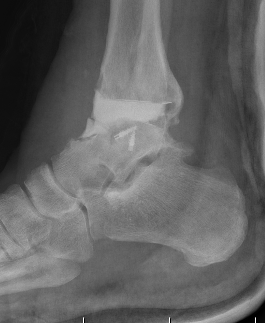

Contraindications

| Absolute | Relative |

|

Infection Charcot Poor soft tissue envelope Severe malalignment or instability Talus AVN > 1/3 |

Malalignment Poor bone stock Obesity Diabetes Smoking |